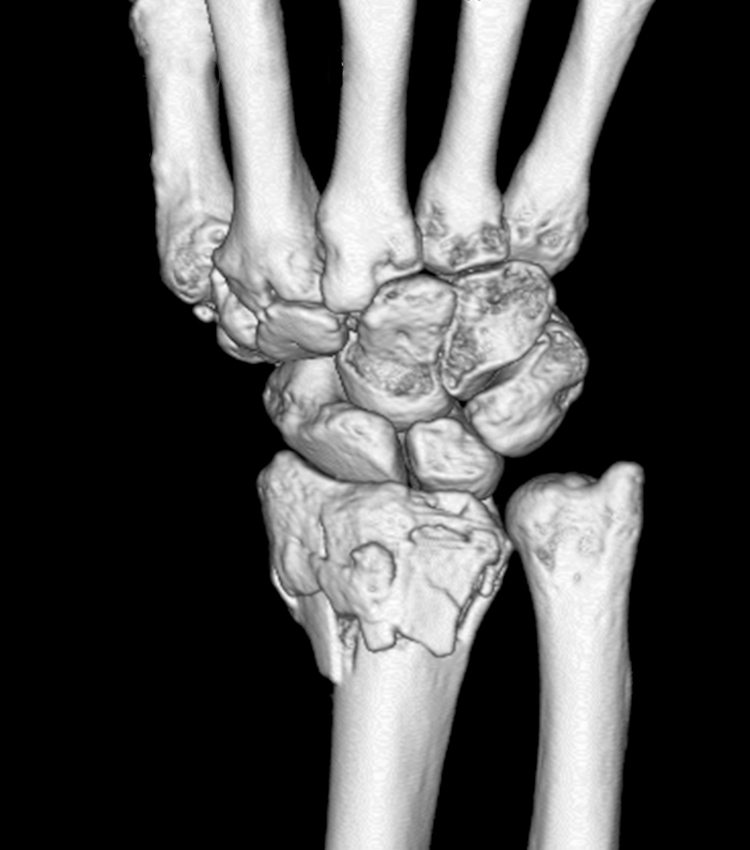

橈骨遠位端骨折

転倒して手をつくことで起こる手首の骨折です。北海道では雪道で滑ることで発生するため冬の期間に多く起こります。まずは痛いのですが、徐々に腫れが出てきます。ズレが大きい場合には手首に変形が見られます。

レントゲンで骨折の状態を確認します。ズレ(転位)が少ない時にはギプスなどの外固定で治りますが、転位が大きく整復してもまたズレてしまう時には手術をお勧めしています(骨接合術)。手術では直視下に骨折を元の位置に戻し専用のチタン製の金属で固定します。その金属は原則として外す必要はありません。